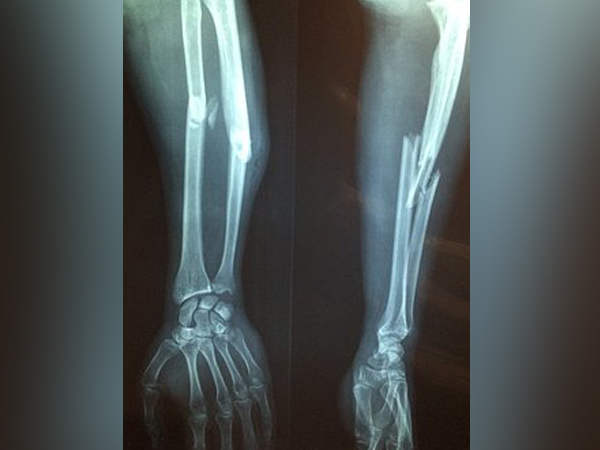

இதுமாதிரி உங்க வீட்ல யாருக்காவது இருக்கா?... இது எதோட அறிகுறினு தெரியுமா உங்களுக்கு?

கம்பார்ட்மென்ட் சிண்ட்ரோம் என்று அழைக்கப்படும் நோய் பற்றிய முழுமையான விவரங்கள் இங்கு உங்களுக்காக பகிர்ந்து கொள்ளப்படுகிறது. அது பற்றிய காரணங்கள் மற்றும் அறிகுறிகளைப் பற்றி விளக்கமாகத் தெரிந்து கொள்ளுங

வாகன விபத்து அல்லது எலும்பு உடைவது போன்ற கடுமையான காயங்களால் இந்த கடுமையான கம்பார்ட்மென்ட் சிண்ட்ரோம் ஏற்படலாம். ஒரு சிறு காயத்திற்கு பின்னும் சில நேரங்களில் இந்த பாதிப்பு வளர்ச்சி அடையலாம். ஆனால் அது மிகவும் அரிது.

. எலும்பு முறிவு

நாட்பட்ட கம்பார்ட்மென்ட் சிண்ட்ரோம் பாதிப்பைக் கண்டறிய மருத்துவர் அந்த நபருக்கு தசைநாண் அழற்சி குறித்த சோதனை அல்லது எக்ஸ்ரே செய்து பார்த்து முழங்காலில் எலும்பு முறிவு உள்ளதா என்பதை ஆராய்ந்து பார்ப்பார். உடற்பயிற்சிக்கு முன்னும் பின்னும் கம்பார்ட்மென்ட்டின் அழுத்த அளவு அளவிடப்பட்டு ஒப்பிடப்படுகிறது.